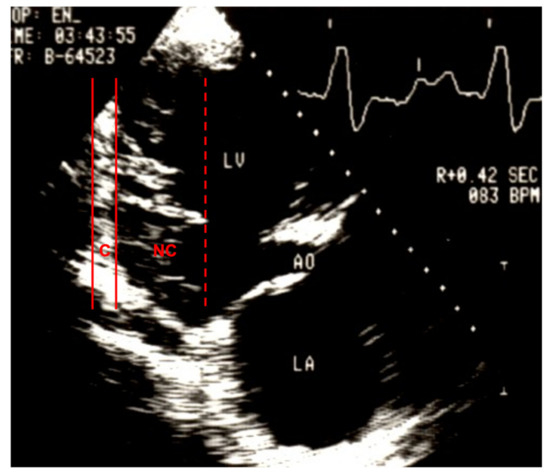

3. The left ventricular wall segments show a typical bilaminar structure, and the noncompact subendocardial layer is at least twice as thick as the compact subepicardial layer in systole; |

| Jenni 2001; [8,78] | Zurich | Excessive prominent trabeculations | Deep intertrabecular recesses | Compacted thin epicardial and much thicker noncompacted endocardial | NC/C > 2 | Abnormalities absent | Perfused recesses in color Doppler | End systole | Short axis view |

| Engberding 2007; [62] | Germany | At least 4 prominent trabeculations | Deep intertrabecular recesses | Bilaminar structure | NC/C ≥ 2 | No other cardiac abnormalities | Blood flow in recesses in color Doppler or with echo contrast | Systole | |

| Petersen 2005; [85] | Trabecular layering | Compacted epicardial and noncompacted endocardial layer | NC/C > 2.3 | True apex excluded | End diastole | Long axis | |